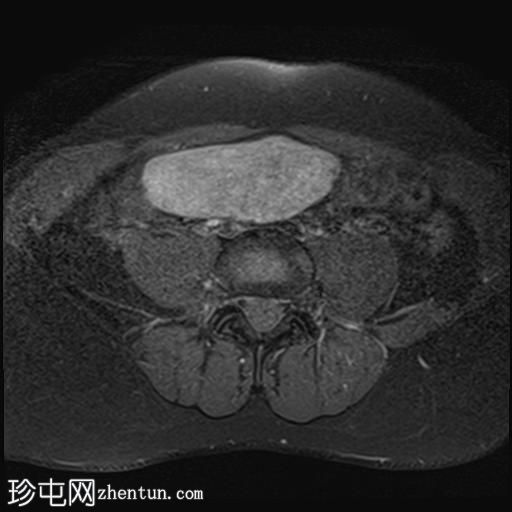

矢状位

T2加权像

盆腔内可见多个边界清晰的肿块:

其中一个位于子宫上方,T2加权像呈中等信号,中心区域呈高信号,增强T1脂肪抑制像未见强化。右侧卵巢增大,增厚的血管蒂扭曲,未见强化,轴位和矢状位T2加权像均显示清晰。

另一个位于子宫后窝,T2加权像呈中等信号,增强扫描显示明显强化。

轻度腹腔积液